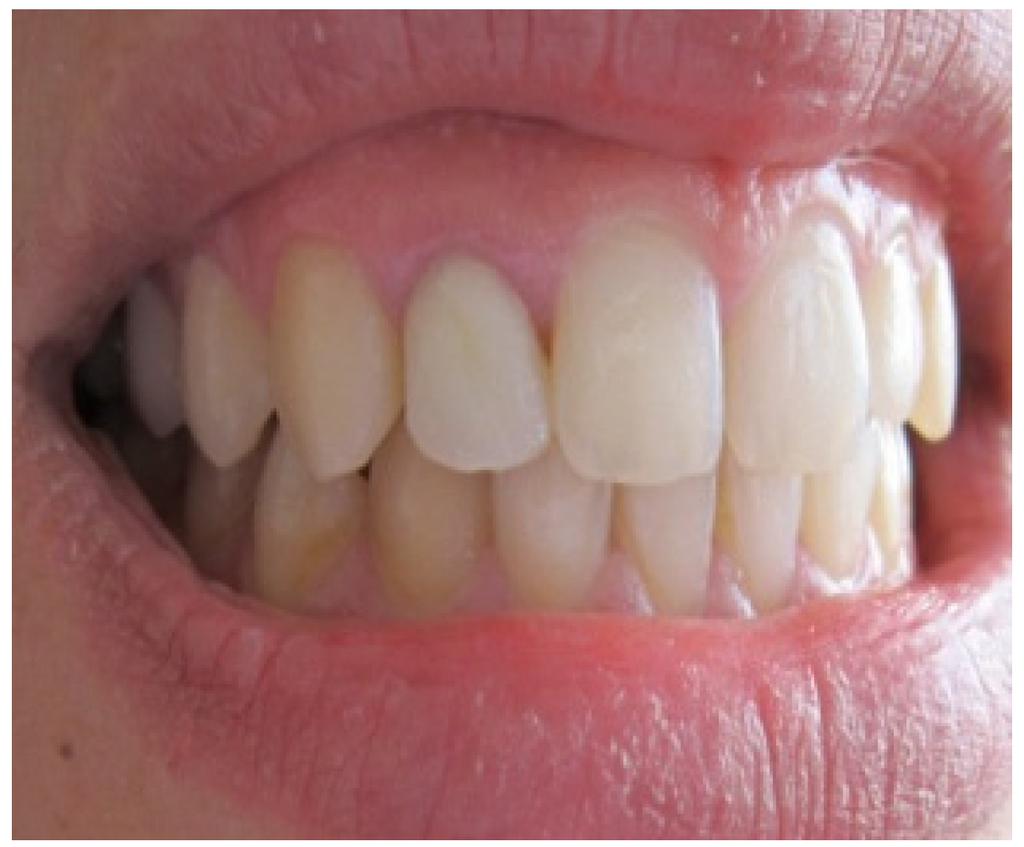

After 4 months of maturation, the abutment tooth was refined after placement and buildup of post and core materials (Figure 6). Later, a full arch impression was taken using a silicone material. An impression of the opposing dentition was also made with irreversible hydrocolloid. The shade was determined with the shade guide (VITA). The final restoration, Zirconia based crown, showing natural appearance with a correct gingival architecture was performed using the CAD/CAM technology. All of the team, including the prosthodontist, periodontist and the ceramist, were satisfied by the result—an aesthetic and functional restoration with a good marginal adaptation and an improved pink and white score (Figure 7). The most grateful of all was, however, our satisfied patient.

Figure 7. Final result showing an improvement of aesthetic appearance.